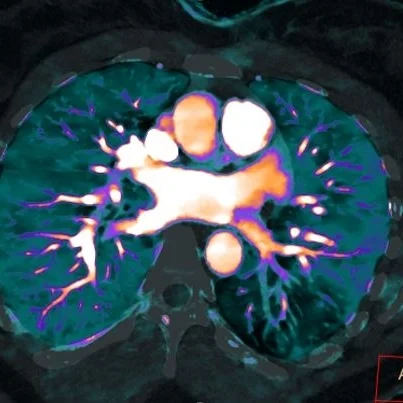

Iodine overlay in oblique axial plane nicely shows the perfusion defect

I think here we see a spectral demonstration of the Euler-Liljestrand mechanism. Bronchial obstruction leads to localized hypoxia, then vasoconstriction with reduced perfusion to the affected bronchovascular territory. Decreased contrast in the draining pulmonary vein proves the vasoconstrictive effect.

The left lower lobe posterior pulmonary veins are hypoenhancing, consistent with vasoconstriction in the vascular bed.